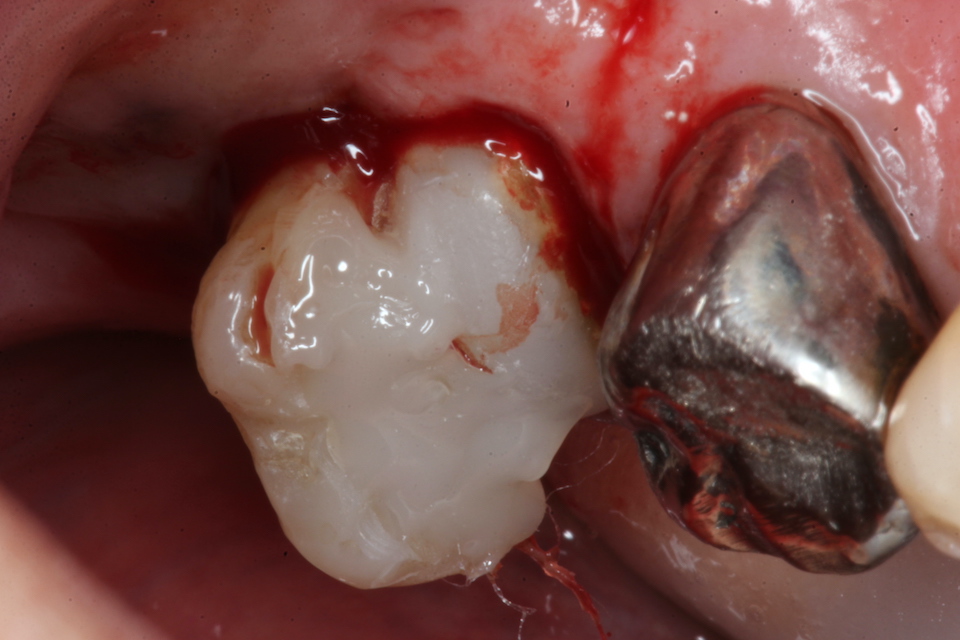

70代男性、左下7、歯根破折、自発痛++

今日は破折した歯根の接着面を新鮮面を出しきれいにしてスーパーボンドの筆積み法で貼り合わせポストを入れてCR併用で再建し、抜歯窩に挿入固定するだけだ。

以下時系列でどうぞ

根管充填材と歯質との間には隙間が存在し、細菌の代謝産物の黒色物質のFeSで覆われている。緊密な充填など絵に描いた餅にすぎない。